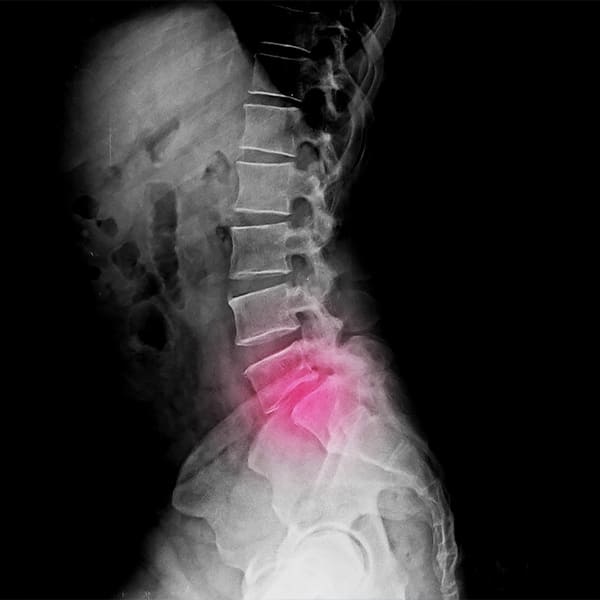

Patologías de columna

Con frecuencia, las enfermedades de la columna provocan dolor cuando los cambios óseos presionan la médula o los nervios. También pueden limitar el movimiento. El tratamiento varía según la enfermedad, pero algunas veces incluyen aparatos ortopédicos para la espalda y cirugía.

Hernia de disco

Afección caracterizada por un problema en el disco cartilaginoso ubicado entre los huesos de la columna vertebral.

Espondilolistesis

Trastorno de la columna vertebral en el que un hueso (vértebra) se desplaza sobre el hueso que está debajo.

Cervicalgia y lumbalgia

Daños o afecciones en músculos, tendones, ligamentos, articulaciones, nervios o vasos circulatorios.

Tratamiento escoliosis

Curvatura lateral de la columna vertebral.

Ciática

Dolor que se extiende a lo largo del nervio ciático, desde la espalda baja hasta una o ambas piernas.